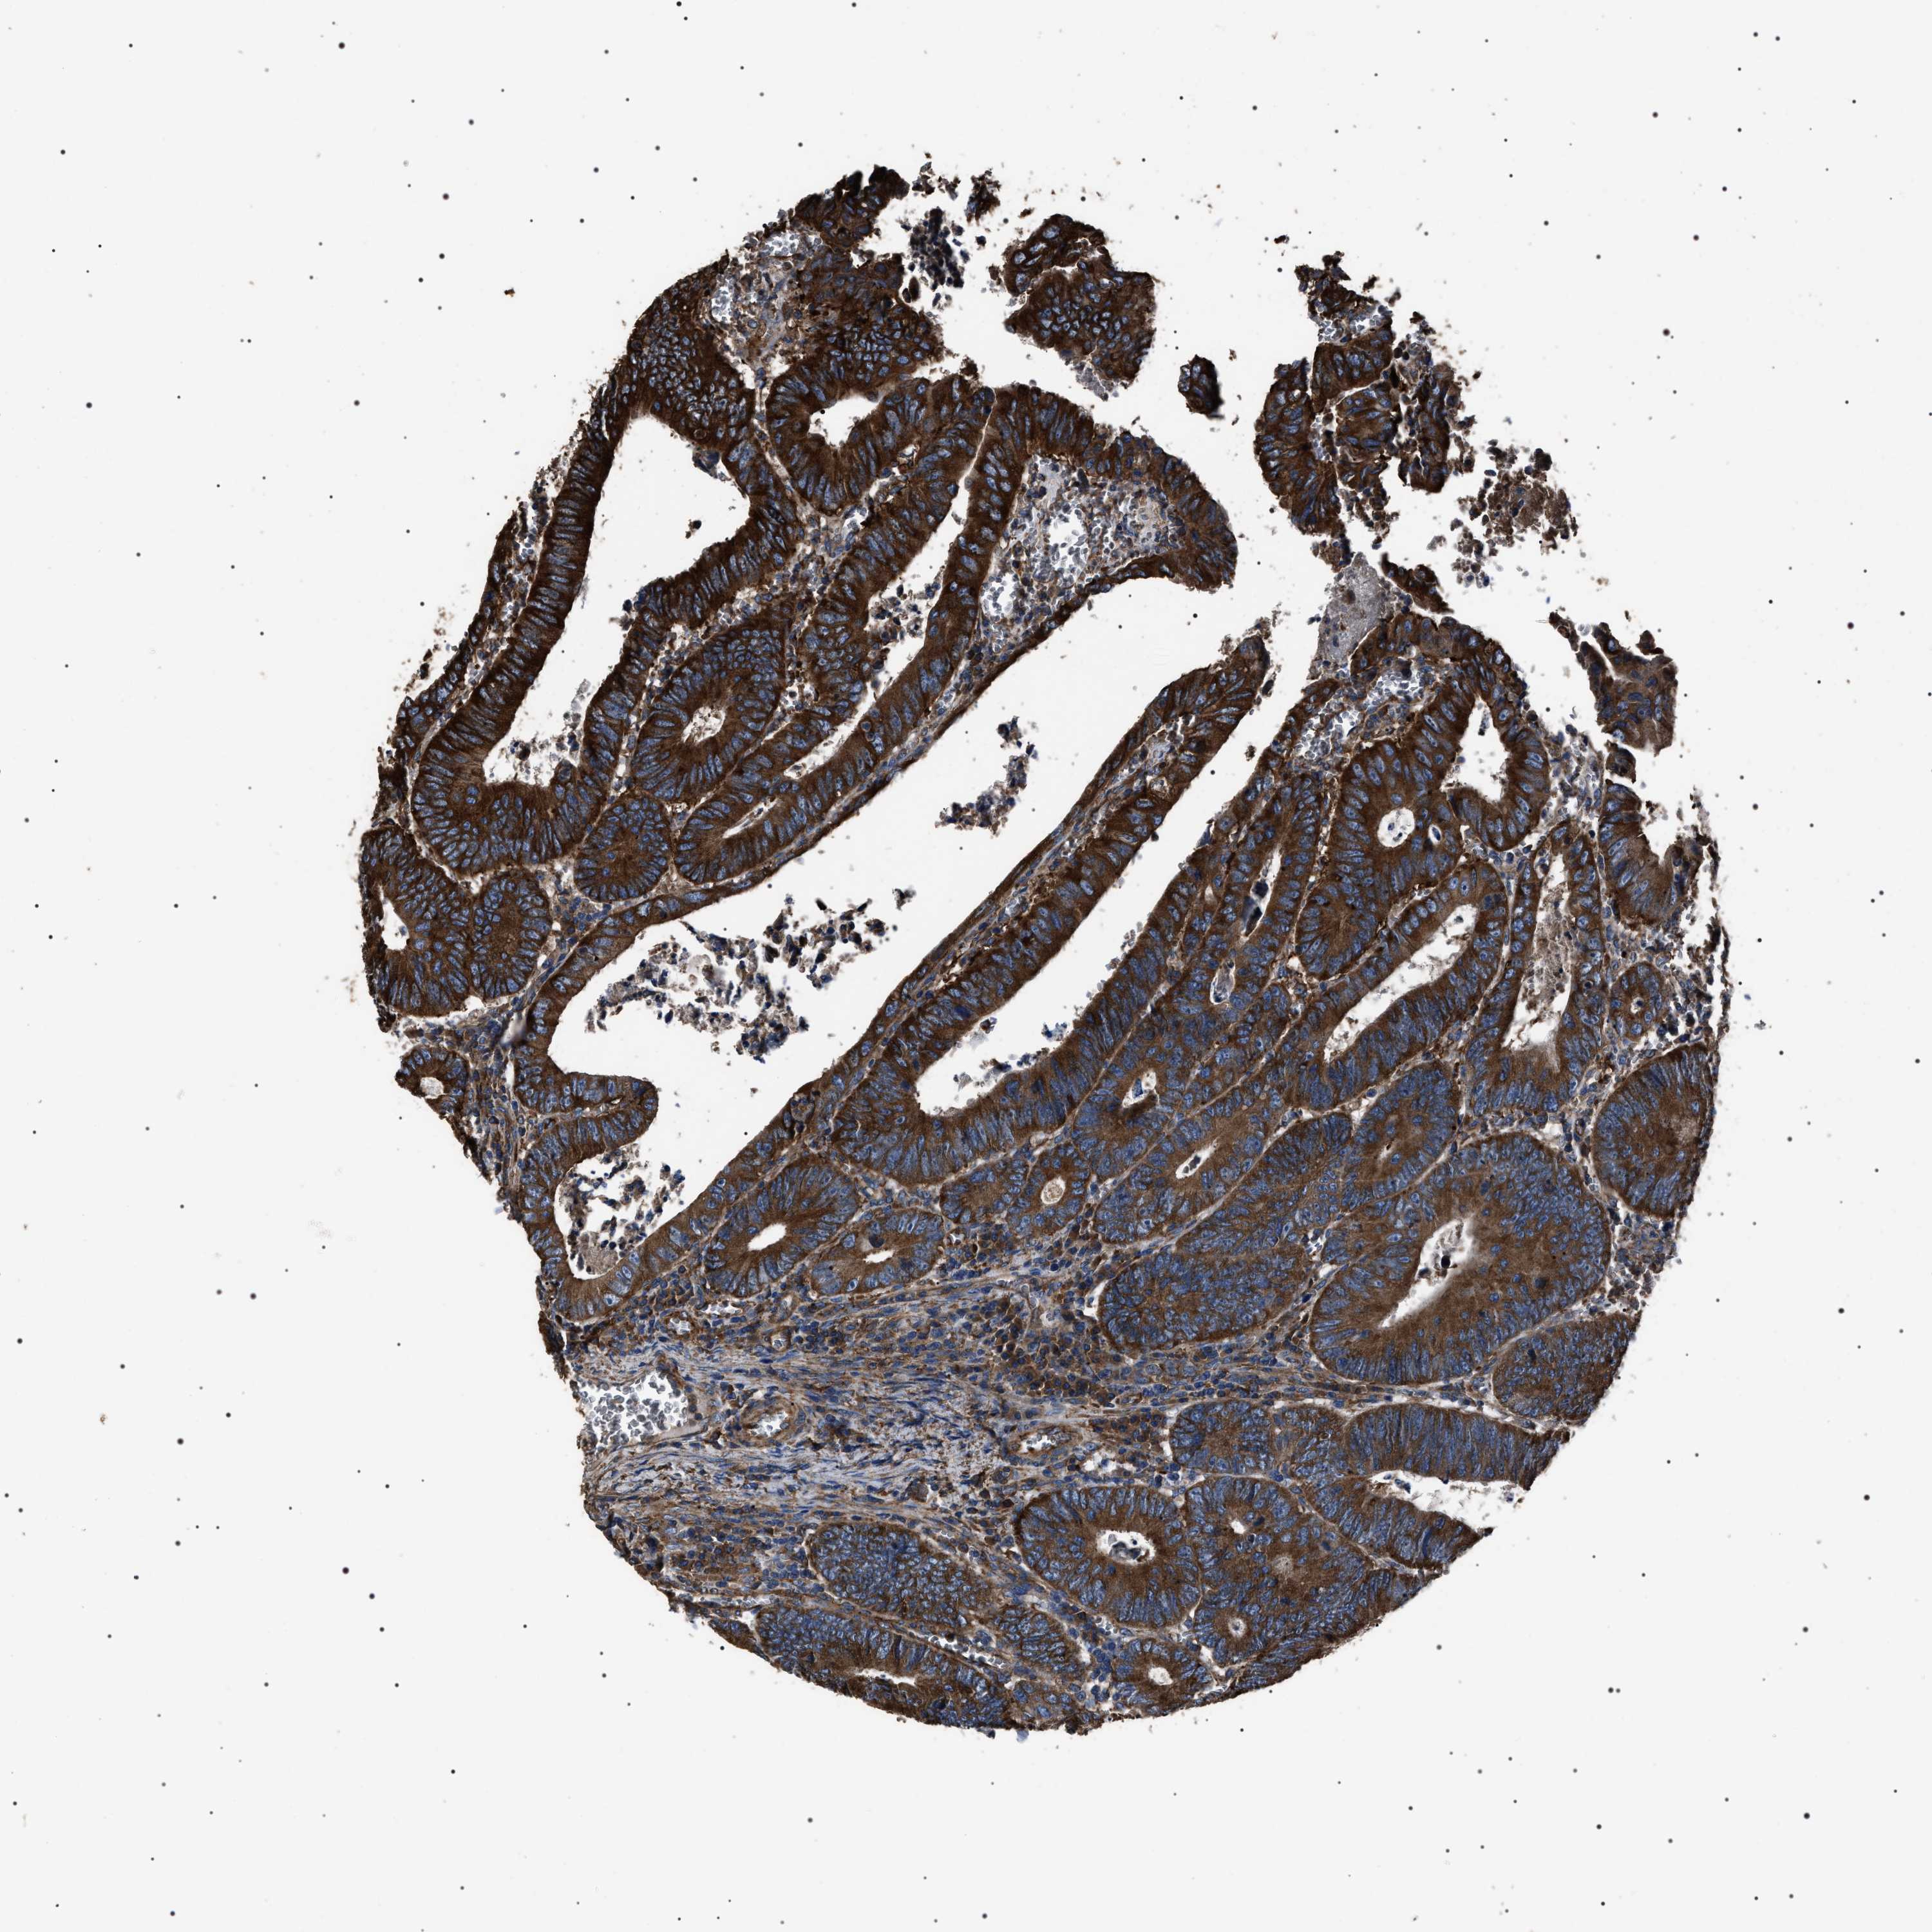

RECTUM ADENOCARCINOMA (TCGA) - Interactive survival scatter ploti

The Survival Scatter plot shows the clinical status (i.e. dead or alive) for all individuals in the patient cohort, based on the same data that underlies the corresponding Kaplan-Meier plots. Patients that are alive at last time for follow-up are shown in blue and patients who have died during the study are shown in red.

The x-axis shows the expression levels (FPKM) of the investigated gene in the tumor tissue at the time of diagnosis. The y-axis shows the follow-up time after diagnosis (years). Both axes are complimented with kernel density curves demonstrating the data density over the axes. The top density plot shows the expression levels (FPKM) distribution among dead (red) and alive patients (blue). The right density plot shows the data density of the survived years of dead patients with high and low expression levels respectively, stratified using the cutoff indicated by the vertical dashed line through the Survival Scatter plot. This cutoff is automatically defined based on the FPKM cutoff that minimizes the p-score. The cutoff can be changed by dragging the vertical line or by entering a cutoff value in the square labeled "Current cut-off".

Under the Survival Scatter plot the p-score landscape (black curve; left axis) is shown together with dead median separation (red curve; right axis). Dead median separation is the difference in median mRNA expression between patients who have died with high and low expression, respectively. It is calculated as follows: median FPKM expression of dead patients with high expression - median FPKM expression of dead patients with low expression. This is intended to aid the user in visually exploring custom cutoffs and the associated p-scores and dead median separation.

Individual patient data is displayed and can be filtered by clicking on one or more of the category buttons on the top of the page. Categories describing expression level and patient information include: high, low, alive, dead, female, male and tumor stages. The scale of the x-axis can be toggled between linear and log-scale by clicking on the "x log" button. Mouse-over function shows TCGA ID, patient information and mRNA expression (FPKM) for each patient.

& Survival analysisi

Kaplan-Meier plots summarize results from analysis of correlation between mRNA expression level and patient survival. Patients were divided based on level of expression into one of the two groups "low" (under cut off) or "high" (over cut off). X-axis shows time for survival (years) and y-axis shows the probability of survival, where 1.0 corresponds to 100 percent.

HSCB is not prognostic in Rectum Adenocarcinoma (TCGA)

Best expression cut offi

Based on the FPKM value of each gene, patients were classified into two groups and association between prognosis (survival) and gene expression (FPKM) was examined. The best expression cut-off refers the FPKM value that yields maximal difference with regard to survival between the two groups at the lowest log-rank P-value. Best expression cut-off was selected based on survival analysis .

When clicking on this number, the vertical dashed line indicating cut-off, the interactive survival plot, and the Kaplan-Meier curve will be adjusted to show results based on the best expression cut-off.

: 6.97

TCGA RNA samplesi

RNA-seq data is reported as average FPKM (number Fragments Per Kilobase of exon per Million reads), generated by the The Cancer Genome Atlas (TCGA) .

Normal distribution across the dataset is visualized with box plots, shown as median and 25th and 75th percentiles. Points are displayed as outliers if they are above or below 1.5 times the interquartile range. FPKM values of the individual samples are presented next to the box plot.

Average pTPM 9.3

Number of samples 88